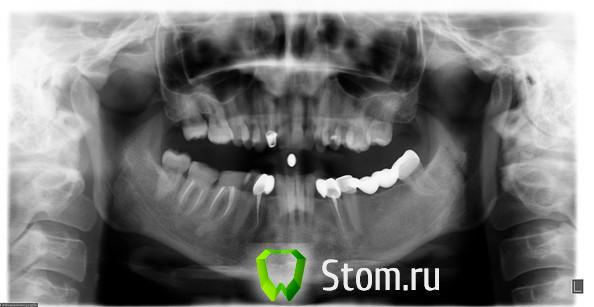

Эндж Опубликовано 25 января, 2012 Поделиться Опубликовано 25 января, 2012 Добрый день! В каком случае передний зуб укрепляют штифтом? Недавно перелечили канал на верхней двойке, поставили временную коронку, впоследствии будет коронка из циркония. Про штифт разговор не заходил. На снимке канал до перелечивания. Ссылка на комментарий